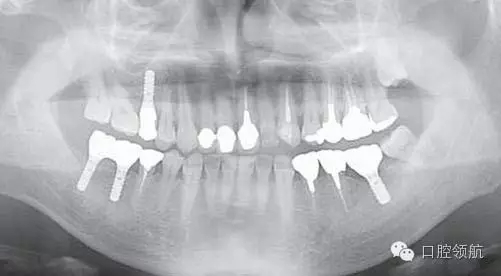

患者,38歲,男性,作為需要全面治療的患者來院?;局委熀?,右下頜磨牙區(qū)及右上頜磨牙區(qū),還有拔牙后的左下頜磨牙缺損區(qū),擬進行種植修復。圖1為初診時的曲面斷層影像,問診,模型診斷,曲面斷層檢查均未見異常,因此,最先在右下頜磨牙缺損區(qū),繼而在右上頜磨牙缺損區(qū)植入種植體,這些種植體愈合良好。

圖1 初診時的曲面斷層影像。